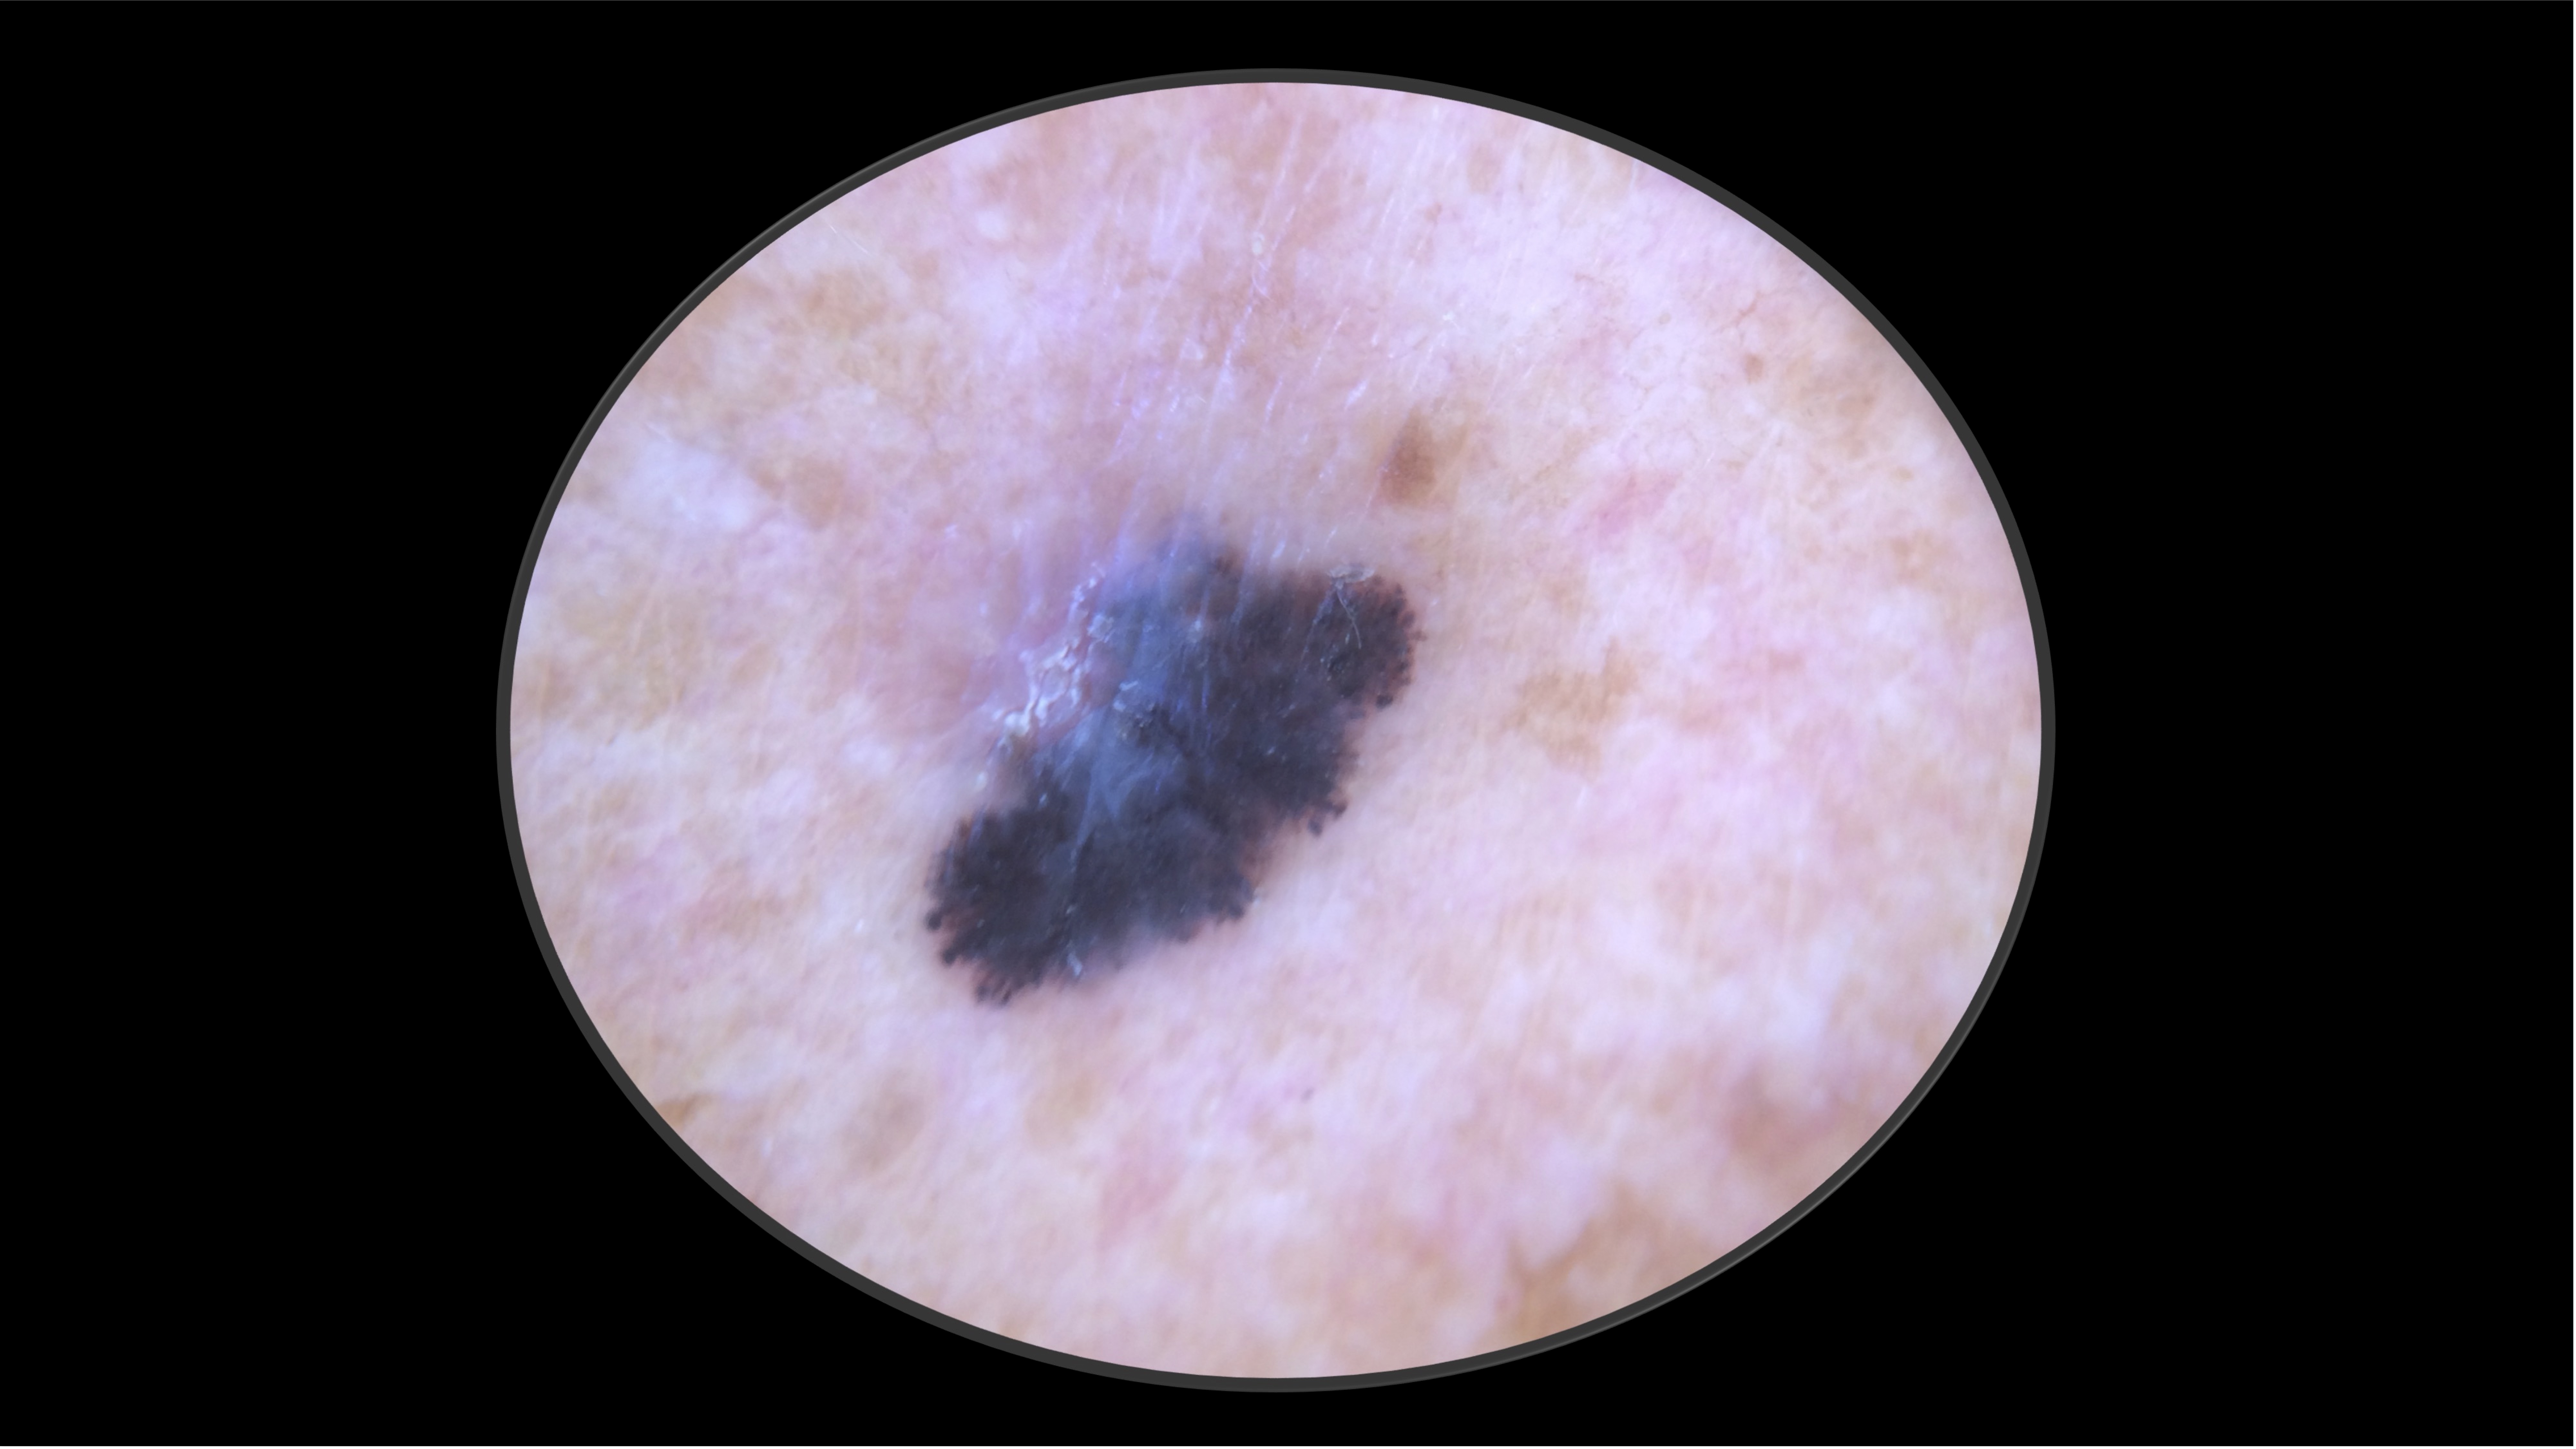

Case 2 - HPI

71-year-old Fitzpatrick skin type 2 male with no significant PMH presents with this lesion on his chest x 3 months

Case 2 - Work Up

- Excisional biopsy performed.

- Pathology revealed a 4.1 mm thick, non-ulcerated, superficial spreading melanoma. Mitotic rate 9 per mm2. LVI present. Tumor infiltrating lymphocytes present, non-brisk. No microsatelites.